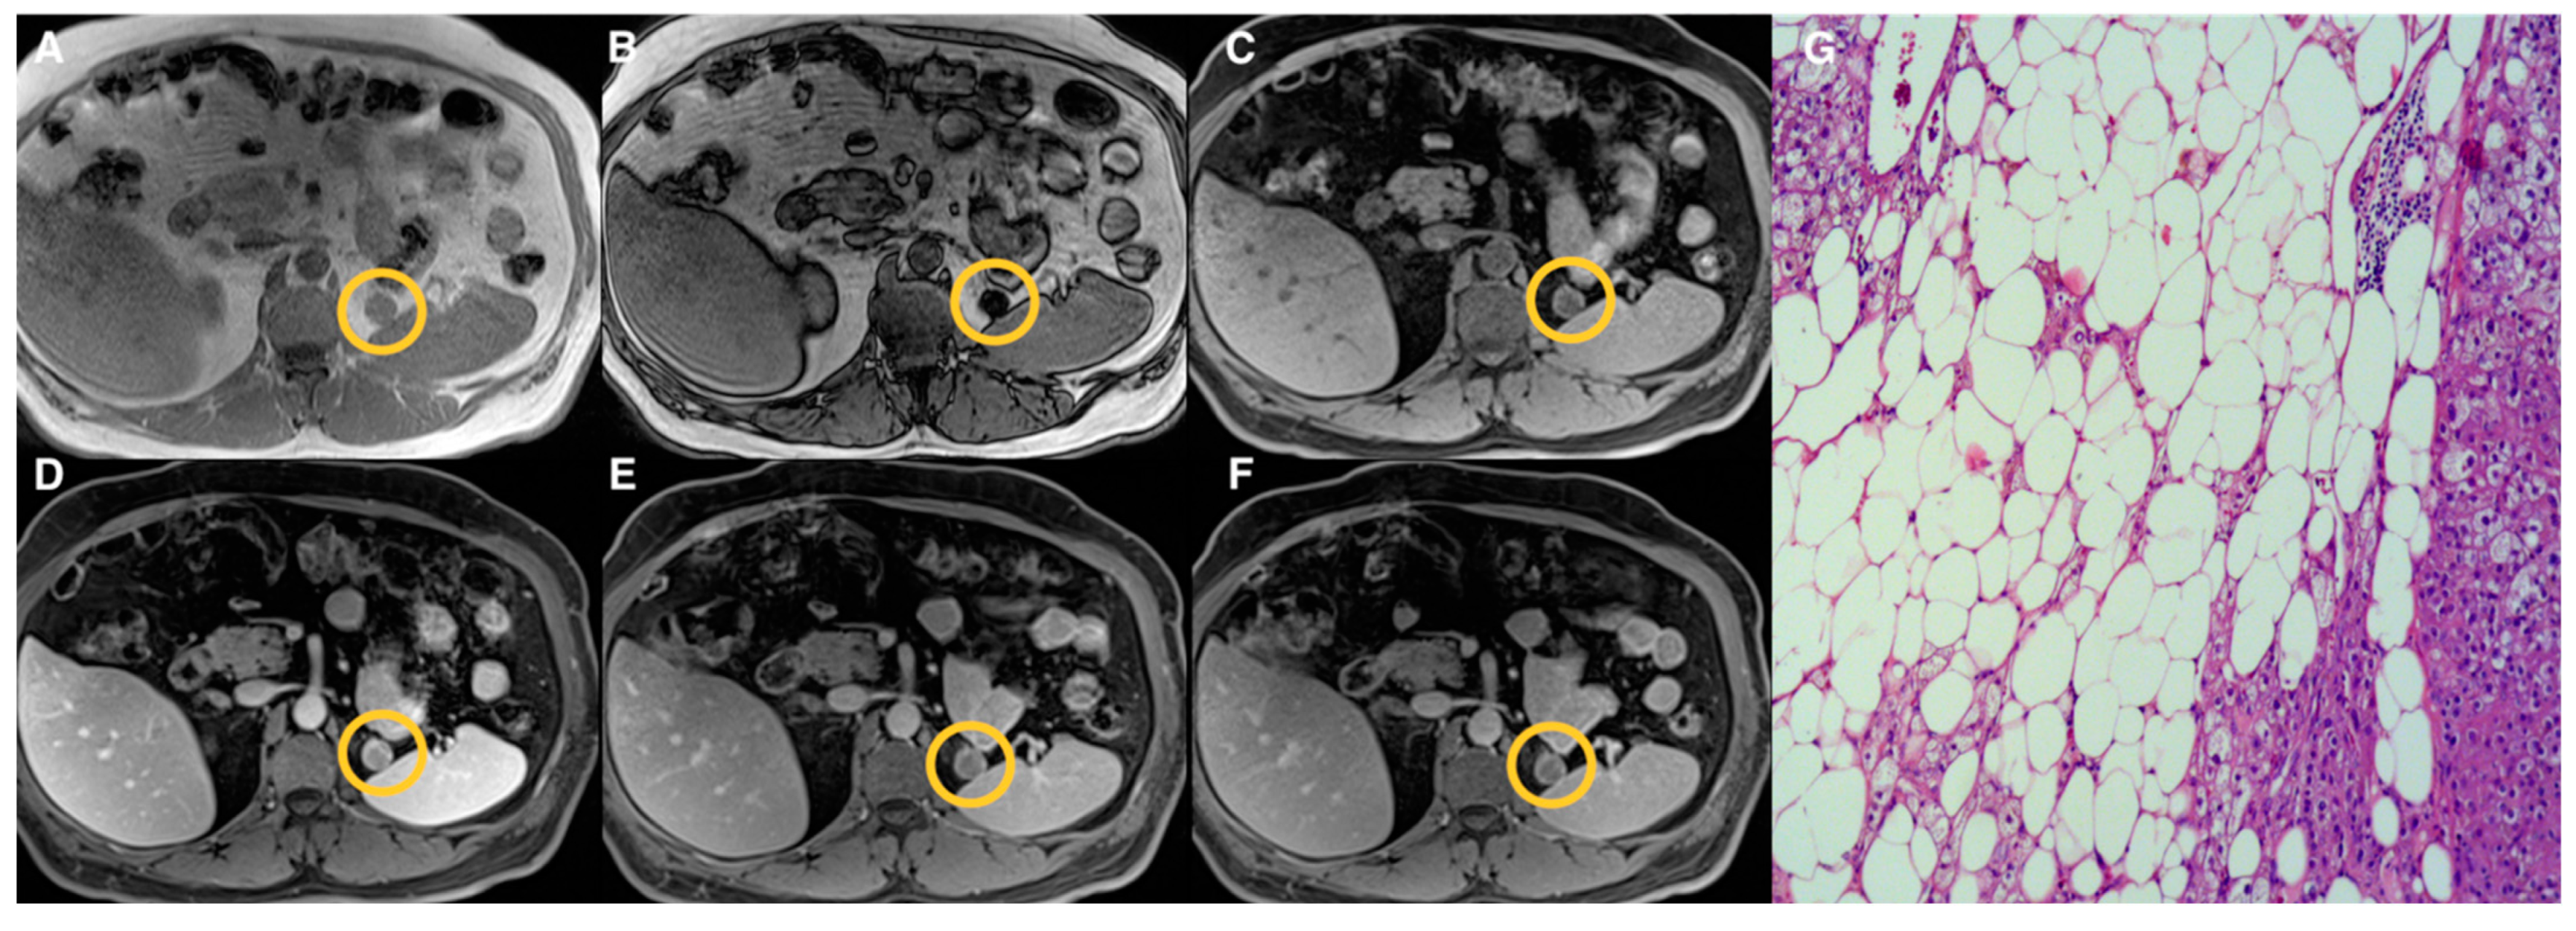

| Groups | Qualitative CS Signal Drop | Lesion Type | Total |

|---|---|---|---|

| 1 | Homogeneous | Adenomas (n = 19) | 19 |

| 2 | Heterogeneous | Adenomas (n = 17) Pheochromocytomas (n = 3) Myelolipomas (n = 3) | 23 |

| 3 | Absent | Adenomas (n = 10) Pheochromocytomas (n = 9) Primary malignant tumors (n = 5) Metastasis (n = 5) Oncocytoma (n = 1) | 30 |